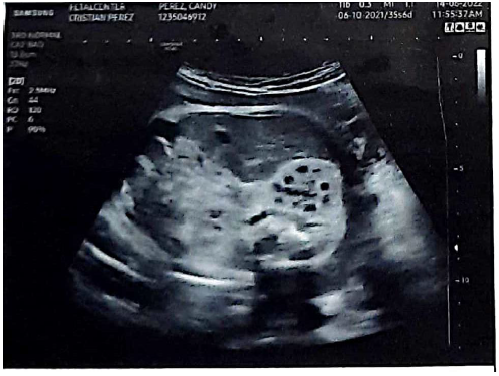

Lactante menor masculino de tres meses de edad, producto del primer embarazo controlado de una madre de 30 años, quien en la semana 36 de gestación se realiza una ecografía obstétrica que muestra imágenes renales fetales hiperecogénicas y de aspecto multiquístico (figura 1).

Fuente: historia clínica aportada por la madre.

Figura 1 Ecografía prenatal en la semana 36 de gestación: muestra del feto con riñones hiperecogénicos y de aspecto multiquístico